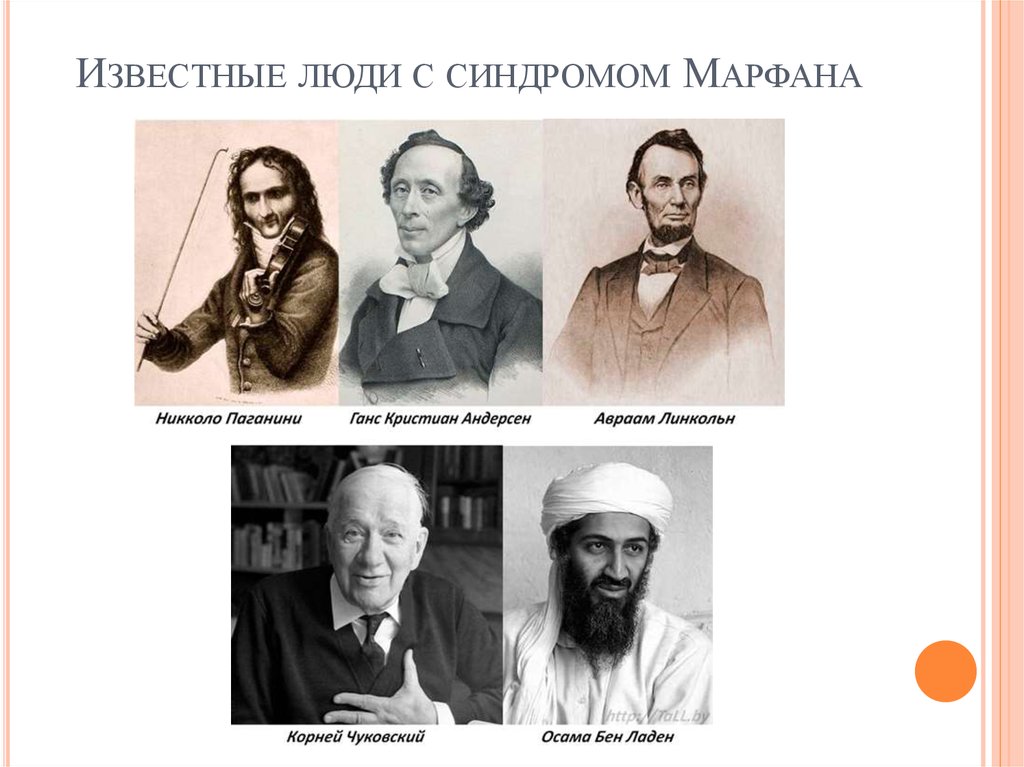

Boleznennyj dar nikkolo paganini redkij sindrom marfana priznaki sposoby lecheniya i nasledovanie u detej sindrom marfana kto bolel iz znamenitostej (Тип файлу jpg)

Boleznennyj Dar Nikkolo Paganini Redkij Sindrom Marfana Priznaki Sposoby Lecheniya I Nasledovanie U Detej Sindrom Marfana Kto Bolel Iz Znamenitostej

Chelovek i ego zdorove sindrom marfana sekrety andersena paganini i chukovskogo obsuzhdenie na liveinternet rossijskij servis onlajn dnevnikov (Тип файлу jpg)

Chelovek I Ego Zdorove Sindrom Marfana Sekrety Andersena Paganini I Chukovskogo Obsuzhdenie Na Liveinternet Rossijskij Servis Onlajn Dnevnikov